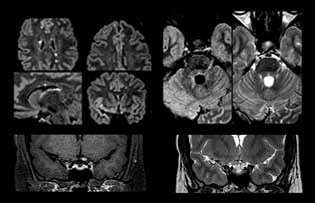

For MS imaging in the brain, Dr. Savatovsky uses 3D FLAIR as the basic sequence to visualize the lesions and assess the situation and lesion load. “We count the lesions in each location to determine if the criteria of the disease are fulfilled. We use a T2-weighted sequence because our neurologists are used to it. We compare the lesion load on FLAIR with a 3D T1 post-contrast sequence to help us determine whether lesions are old or new. We typically administer the contrast before the patient enters the machine because it shortens the examination time and allows to visualize active lesions that tend to be more visible after several minutes. When a differential diagnosis is difficult, we add sequences such as susceptibility imaging, because some focal MS lesions have a small vein in the center[3].”

“The biggest challenges are properly characterizing the lesion and giving the surgeon all the information needed, such as the location of vessels and functional areas. Sometimes a very comprehensive exam is necessary, such as when a mass has been discovered at another hospital after which the patient is referred to us. We then do both lesion characterization and preoperative imaging in one exam, so both morphologic and functional assessment. For morphologic assessment we will use pre- and post-contrast T1-weighted imaging, FLAIR to assess infiltration, and diffusion. For functional characterization we will perform perfusion, spectroscopy, and susceptibility weighted imaging to look for micro vessels or micro hemorrhage inside the lesion[4]. For preoperative imaging we perform specific morphologic imaging that is compatible with the navigation system; depending on the location of the tumor, we would do fMRI or DTI.”